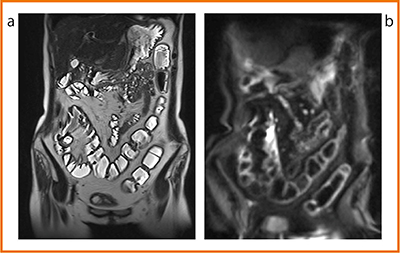

3T TRILLIUM OVALの画像で特筆すべきは,明瞭な拡散強調画像である。図1は,内視鏡で病変が認められなかった症例である。single-shot fast spin-echo(図1 a)でも異常所見は見られないが,拡散強調画像(図1 b)では明瞭な高信号として描出されている。1.5Tでは異常のない腸管はほとんど描出されないことが多いが,3Tの良好な信号雑音比(SNR)を反映していると言えるだろう。病変と間違えないように注意が必要である。

図1 正常例

a:single-shot fast spin-echo

b:拡散強調画像(b=800)